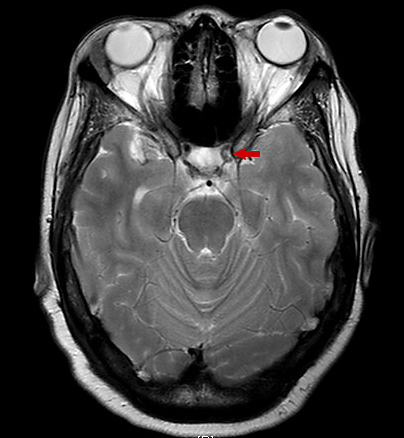

Findings of an MRI scan of the head were significant for multifocal bilateral subacute infarcts, predominantly scattered throughout the left cerebral hemisphere with superimposed multifocal remote infarcts, and vessel occlusion (Figures 1-3).

Figure 3. T2-weighted MRI scan showing decreased contrast flow through the left internal carotid artery, consistent with stenosis and infarcts identified in Figures 1 and 2.

Cerebral angiography was then performed to further clarify the MRI findings; the results showed severe stenosis of the right and left middle cerebral and anterior cerebral arteries (Figure 4).